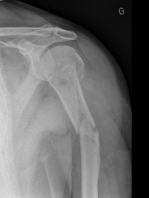

Malgré la regrettable fracture du cuisinier mardi matin 1er janvier, une cuisinière remplaçante s'est proposée et a su ravir les estomacs de tous nos gloutons, affamés par les journées de ski. Le cuisinier est rentré chez lui après une solide opération et il se remet dès à présent de ce malencontreux accident, survenu, même pas sur les pistes, mais devant le chalet, sur une plaque de glace particulièrement glissante !